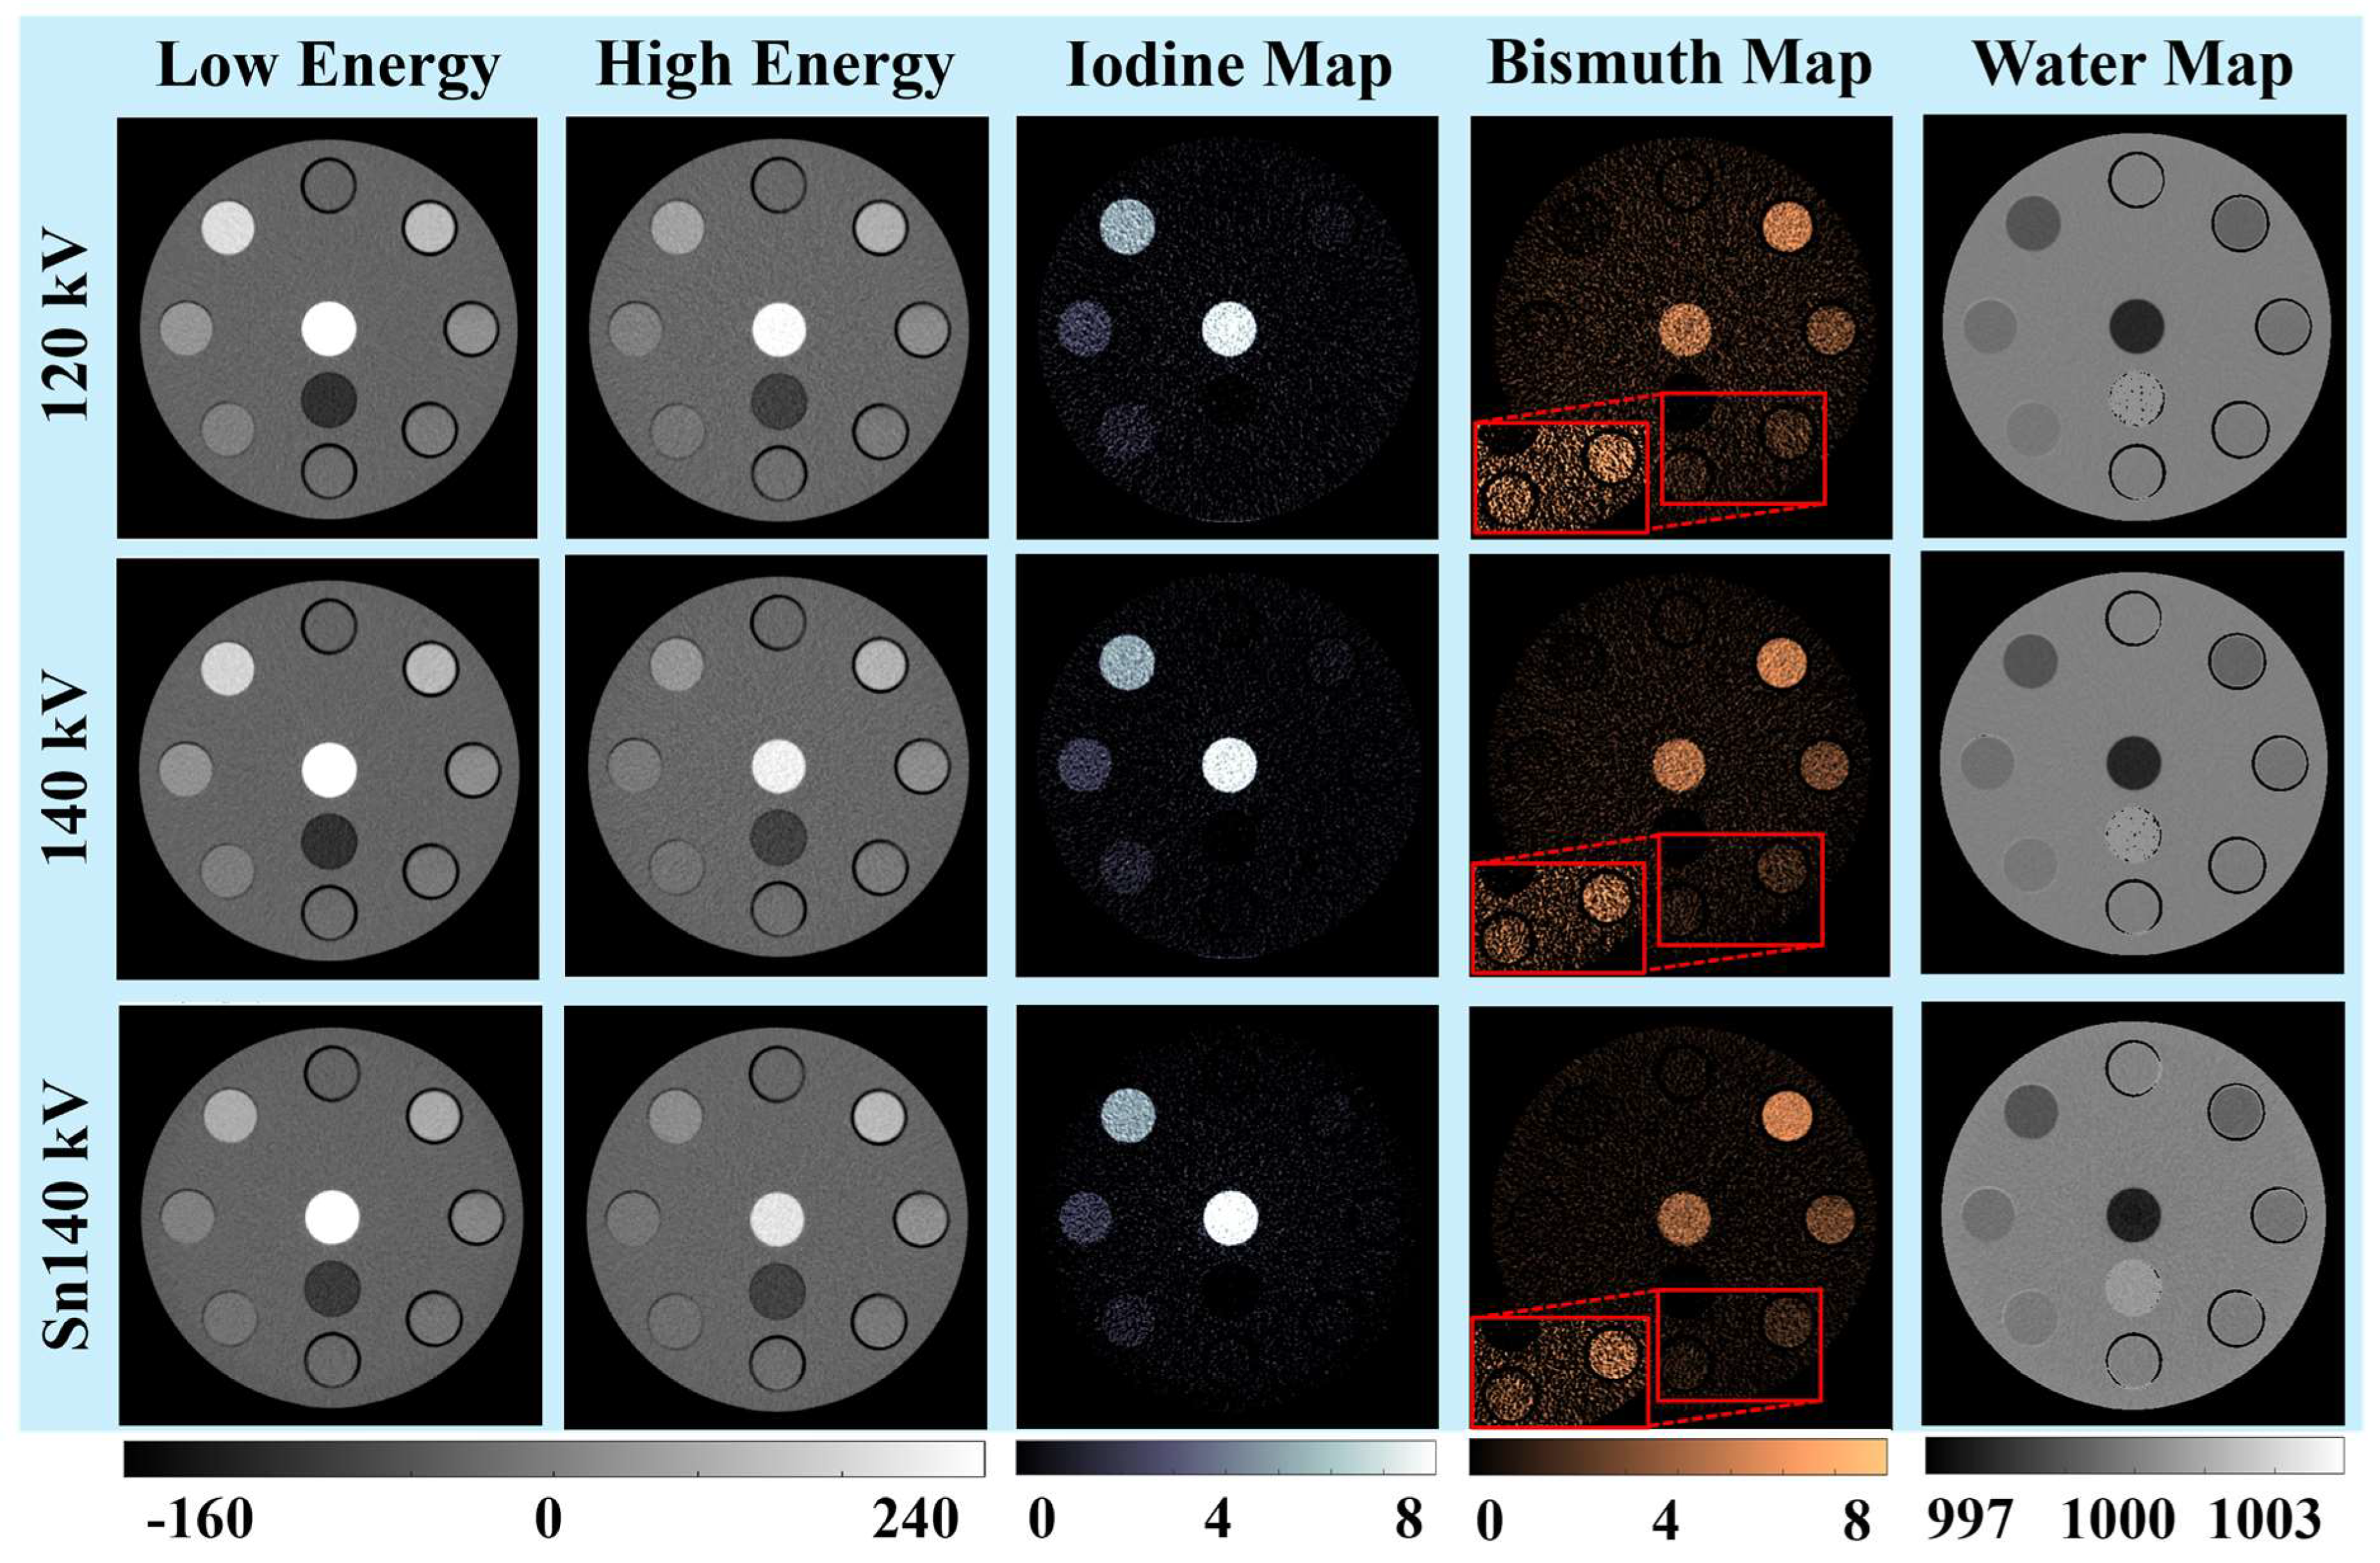

3.1. Visual and Qualitative Evaluations

3.1.1. Iodine and Bismuth Separations

3.1.2. Signals and Noises

3.1.3. Low-Concentration Materials